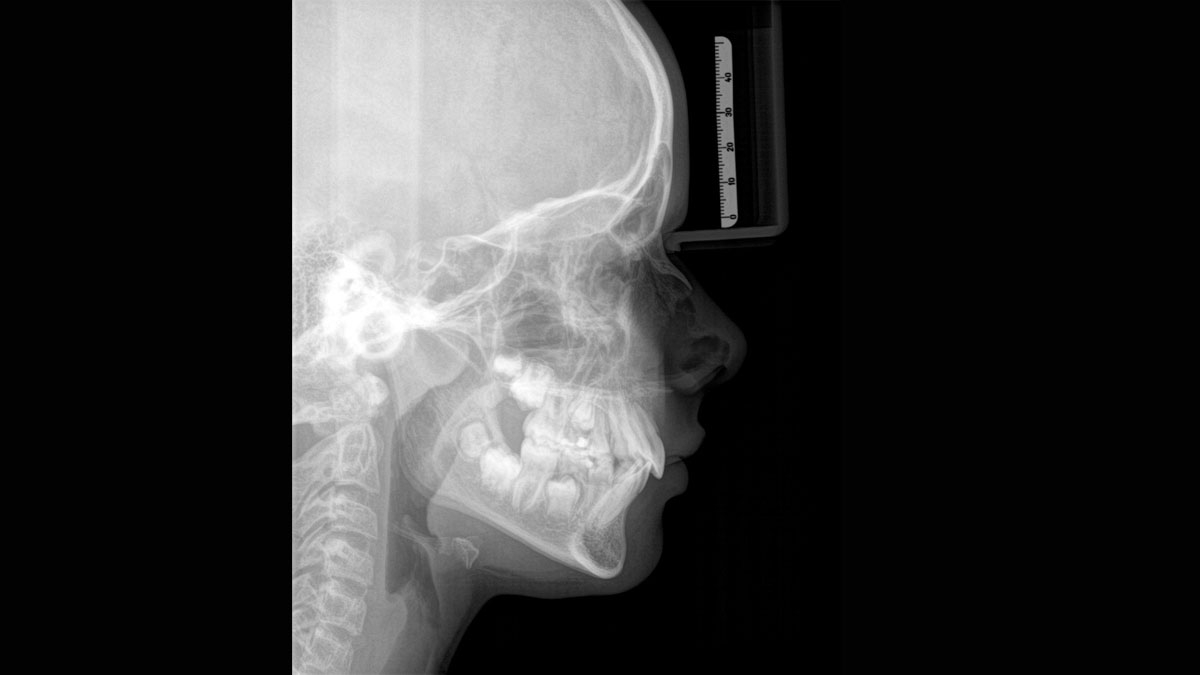

When trying to capture a successful medical or dental X-ray there is an ongoing fundamental conflict. On the one hand, you want to do whatever it takes to acheive maximum image quality, on the other hand, the radiation dose should be as low as reasonably achievable for the patient. At Dentsply Sirona we are dedicated to offering products that ensure exceptional image quality while supporting safe and ethical practice. When developing our products, we observe the internationally valid ALARA principle (as low as reasonably achievable).

Thanks to the optimized low dose mode with a dedicated filter, the imaging of dense structures, such as bones, is possible at a greatly reduced dose. This makes Intelligent Low Dose an attractive and efficient option for many clinical situations. Whether in orthodontics or implantology - with Dentsply Sirona solutions you will find the optimum setting for every case.